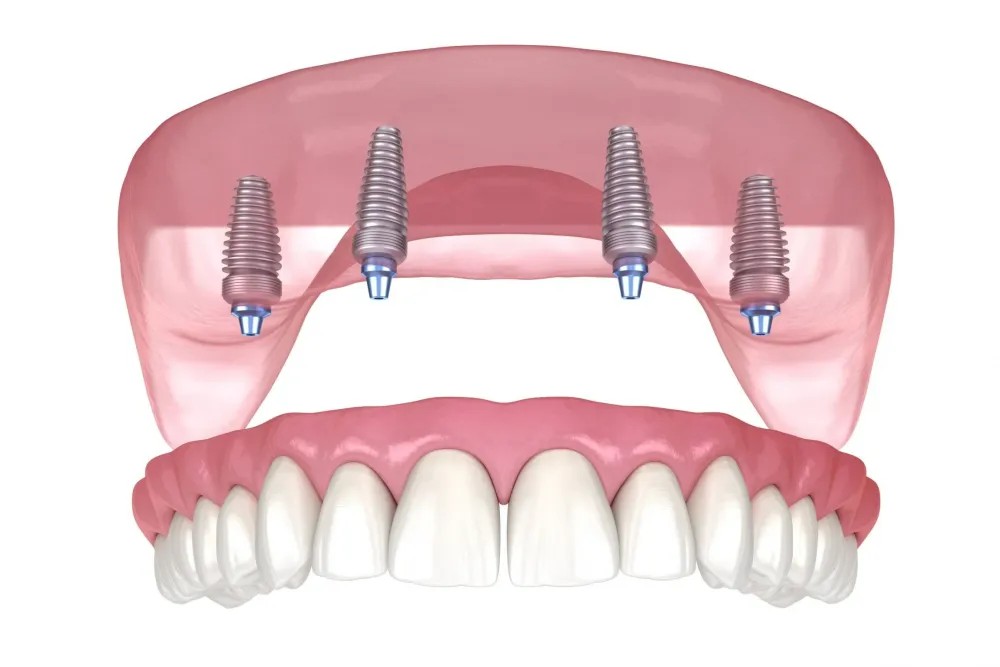

Cosmetic Dentistry & Hollywood Smile

Founded in 2015, our dental clinic in Istanbul is dedicated to providing high-quality dental care through advanced techniques and personalized treatment. Renowned for cosmetic and restorative dentistry, we ensure each patient's comfort, safety, and satisfaction with every visit.